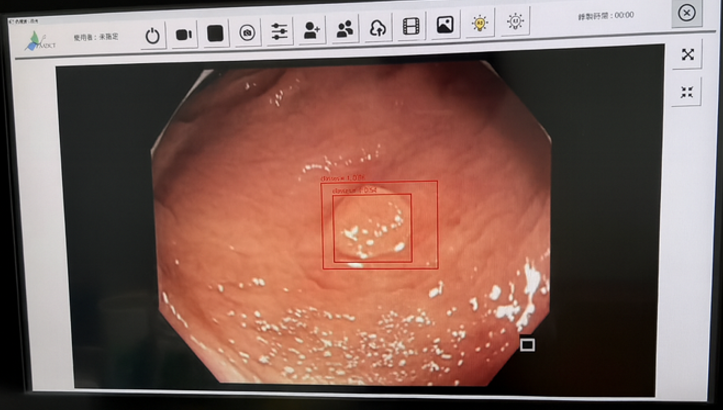

宸祿科技聚焦AI醫療影像,首創12 mm一次性雙鏡頭影像融合大腸內視鏡,三畫面同步顯示並以深度學習即時標註病灶,將早期癌檢出率提升40%。一次性耗材避免交叉感染並省下昂貴清洗,最適合日趨嚴格的感染管制。 產品採可回收材料,每支鏡體減碳25%,符合ESG永續醫療。

•早期癌(扁平病灶)有將近50%會被忽略而延誤診斷— 需要即時 AI 協助

• 高風險病灶需更迅速辨識,降低死亡率